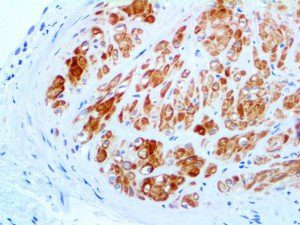

It is the ICU physician who is most likely to witness one of the deadliest manifestations of the abnormal immunological response, the cytokine storm syndrome (CSS). This response is also referred to by some as the cytokine release syndrome (CRS). CSS is characterized by continuous activation and expansion of macrophage and lymphocyte populations, which secrete large amounts of cytokines, causing the cytokine storm. This massive cytokine release is akin to hemophagocytic lymphohistiocytosis (HLH) disease, a syndrome characterized by initial unchecked and persistent activation of cytotoxic T lymphocytes and NK cells.

Clinical and laboratory manifestations of HLH include fever, enlarged liver and/or spleen, neurologic dysfunction, coagulopathy, liver dysfunction, cytopenias (i.e., low levels of erythrocytes, leukocytes, and/or platelets), hypertriglyceridemia, hyperferritinemia, hemophagocytosis, and eventually diminished NK cell activity as the immune system becomes progressively paralyzed. HLH can be familial (primary HLH) or secondary to another disease process (sHLH), such as rheumatic disease, in which it is referred to as macrophage activation syndrome (MAS, characterized by elevated ferritin).